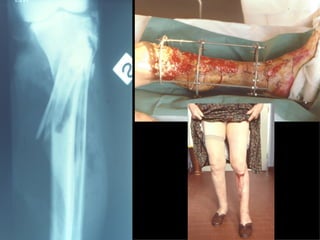

MIPPO

Dal Gennaio 2000 al Febbraio 2006 abbiamo trattato 167 fratture chiuse  con placca percutanea  in 164 pazienti :  27 lesioni diafisarie di gamba, 12 piloni tibiali ,  11 fratture prossimali di tibia, 36 fratture sovracondiloidee di femore, 17 fratture diafisarie di femore, 43 fratture metaepifisarie prossimali di omero, 21 diafisarie d’omero.  156 guarigioni 8 fallimenti

I buoni risultati ottenuti dipendono da 5 punti fondamentali:   una accurata riduzione percutanea della frattura  precise vie di accesso  l’utilizzo della placca che consenta il più lungo braccio di leva possibile il pretensionamento della placca  una sintesi con un ridotto numero di viti

Accurata riduzione percutanea della frattura

Fratture  esposte

VANTAGGI CHIRURGIA MININVASIVA Mini Open Inserimento della placca sottocutaneo per scivolamento Viti percutanee Preservazione dei tessuti molli Ridotto danno vascolare Rapida ripresa funzionale